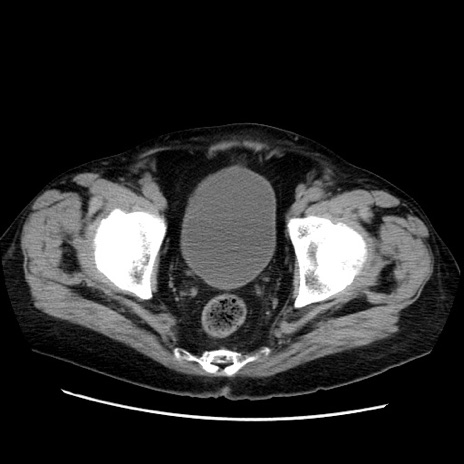

冠状断像

【症例】70歳代男性

【主訴】腹痛

【現病歴】肝硬変・肝細胞癌にてかかりつけの方。約9時間前に食後より腹痛出現。症状が徐々に増悪し、嘔吐出現したため来院。

【既往歴】肝硬変、肝細胞癌(RFA、TACE後)